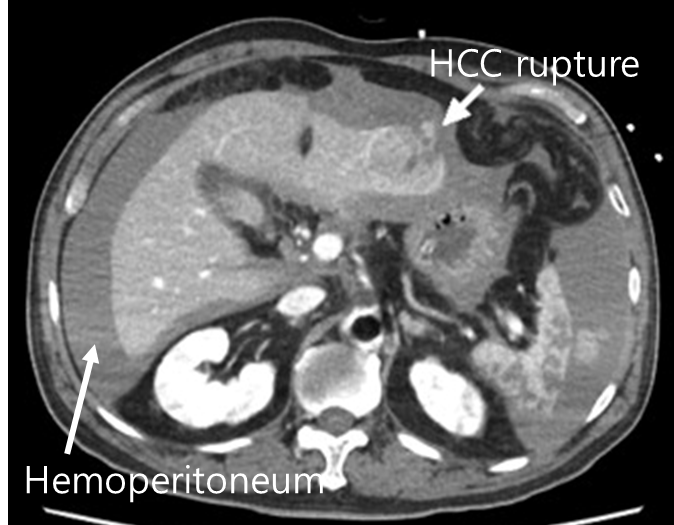

1) 파열 및 출혈

(1) 임상양상: 갑자기 발생하는 복통 → 이후 복부팽만 및 hypovolemic shock

① 복부팽만: 출혈 및 hemoperitoneum에 의해 발생

• 이동둔탁음 등 복수와 유사한 양상 보일 수 있음

② Hypovolemic shock: 어지러움, 저혈압, 빈맥, 빈혈 등

(2) 진단

① CT: HCC의 크기, 위치, 출혈량 등을 전반적으로 파악 가능

② US: 빠르게 intraperitoneal fluid(= hemoperitoneum) 확인 가능

(3) 치료

① 간동맥색전술(hepatic artery embolization): 인터벤션 시술을 통한 빠른 지혈

② 수술: 간동맥색전술이 실패했을 때